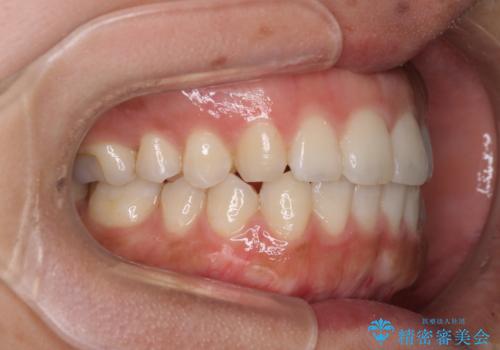

全く目立たないワイヤー矯正 上下リンガル矯正

- 上下の前歯のでこぼこを気にして来院された患者様です。

結婚式が近いこともあり、全く目立たない裏側矯正により口元を整えることとしました。

下顎が左側にずれているため、裏側矯正ということもあり咬み合わせを整えるのに時間がかかってしまいました。